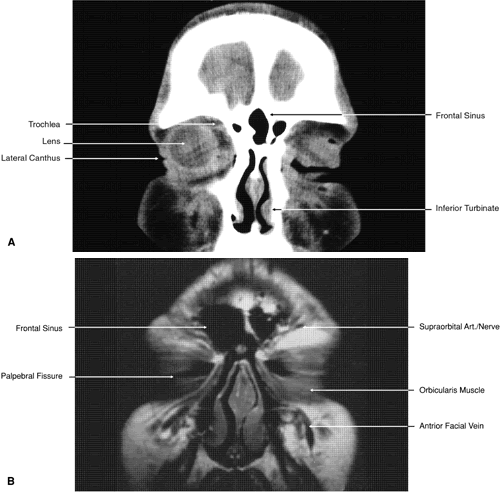

Fig. 17. Coronal images through anterior orbit. A. Computed tomography scan. B. T1-weighted magnetic resonance imaging.

Fig. 18. Coronal images through midglobe. A. Computed tomography scan. B. T1-weighted magnetic resonance imaging.

Fig. 19. Coronal images through midorbit posterior to the globe. A. Computed tomography scan.B. T1-weighted magnetic resonance imaging.

Fig. 20. Coronal images through orbital apex. A. Computed tomography scan. B. T1-weighted magnetic resonance imaging. C. Anatomic section of a cadaver head at the level of the orbital apex.

Fig. 21. Coronal images through optic canal. A. Computed tomography scan. B. T1-weighted magnetic resonance imaging.

Fig. 22. Axial images at the level of inferior orbit. A. Computed tomography scan. B. T1-weighted magnetic resonance imaging.

Fig. 23. Axial images at the level of midorbit. A. Computed tomography scan. B. T1-weighted magnetic resonance imaging.

Fig. 24. Axial images at the level of superior orbit. A. Computed tomography scan. B. T1-weighted magnetic resonance imaging.

Fig. 25. Axial images at the level of tendon of the superior oblique. A. Computed tomography scan. B. T1-weighted magnetic resonance imaging.

Fig. 26. T1-weighted magnetic resonance imaging; sagittal image through optic nerve.

Fig. 27. Coronal images through cavernous sinus and optic chiasm. A. T1-weighted magnetic resonance imaging through anterior chiasm. B. Computed tomography image through anterior chiasm. C. Computed tomography image through posterior chiasm. D. Computed tomography image through optic tract.